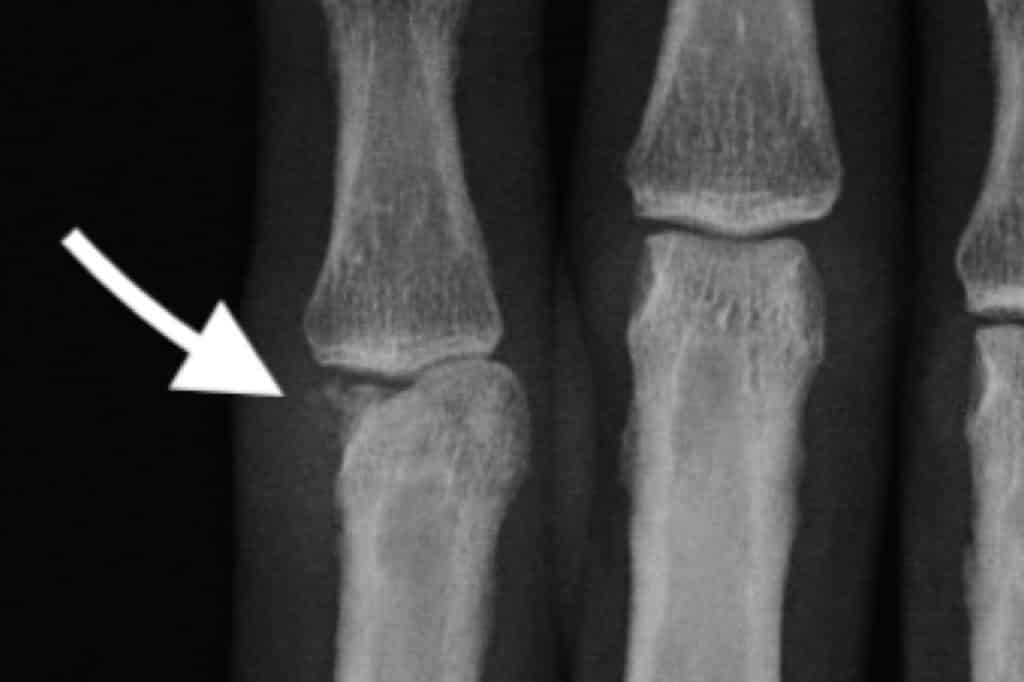

Los huesos del carpo son los pequeños huesos que forman la muñeca. Las fracturas en esta zona pueden afectar la movilidad y estabilidad de la muñeca.